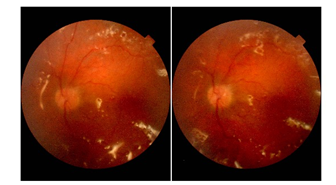

This is a case of 24 years old boy who presented to us due to rapidly progressive deterioration of vision in both eyes over a period of 3 months. His past medical history included a diagnosis of Tourette syndrome (TS) and depression since the age of 14 years. He was not compliant to his medical therapy for fast 1 year. His mother noticed that he was confined to his room for past few days and was stumbling upon the objects at home. She described his motor tics as having blepharospasm, clapping, gouging his fingers into his eyes, and punching himself in the periorbital area. She decided to seek ophthalmologist opinion when she noticed exacerbation in the tic frequency and severe periorbital ecchymosis over the right eye. During the examination, patient was well oriented, did not show any vocal or motor tics and no signs of cognitive impairment. On ocular examination, there was periorbital ecchymosis in the right eye and multiple mechanical scratch marks in the periorbital region laterally and also on face (Figure 1). The nature of the external injuries was commensurate with a tendency of motor tics described by his mother. Ocular movements were full and free. Visual acuity was no perception of light in the right eye and hand movement close to face in the left eye. Slit lamp biomicroscopy showed clear cornea in both eyes (Figure 2). Right eye examination revealed posterior synechiae with near total cataract. There was evidence of KPs, mild aqueous cell and posterior sub capsular cataract in the left eye. Even though the fundus visibility was limited by vitreous hemorrhage, a total retinal detachment with proliferative vitreoretinopathy could be seen in his both eyes (Figure 3). Echography revealed a closed funnel retinal detachment in both eyes (Figure 4).

Figure 3 Anterior segments photographs.

Prognosis of vision in the right eye was nil and explained to the patient. Left eye was managed with phacoemulsification pars plana vitrectomy, endolaser and injection of silicone oil. Intraoperatively, there was inferotemporal dialysis extending from 4.00 to 7.00 o clock position. There was extensive subretinal glial proliferation and preretinal membranes. Peripheral vitrectomy was performed with scleral depression and endolaser was performed. Because of the difficulty of maintaining a facedown position and the possibility of further self-injury, an encircling silicone belt was placed, and the eye was filled with high viscosity silicone oil. Early postoperative phase was uneventful and visual acuity improved to 20/100 with +4.00 Dsph. Patient was advised to take protective polycarbonate glasses and to patch the eye with plastic shield during sleeping. After 4 months patient presented with sudden decrease of vision in the left eye following uncontrollable punching and jabbing in the left eye. On examination, there were small bubbles of silicone oil in the anterior chamber (Figures 5&6). Retina appeared attached (Figures 7&8). Patient underwent membrane peeling with silicone oil removal after psychiatric consultation and modification of medical therapy for TS. At 6 months, the retina remained attached and the visual acuity was 20/100 in the left eye.

Figure 7 Attached retina with silicone oil in situ - 3 month post operative photo.

Figure 8 Attached retina with silicone oil - 6 month post operative photo.